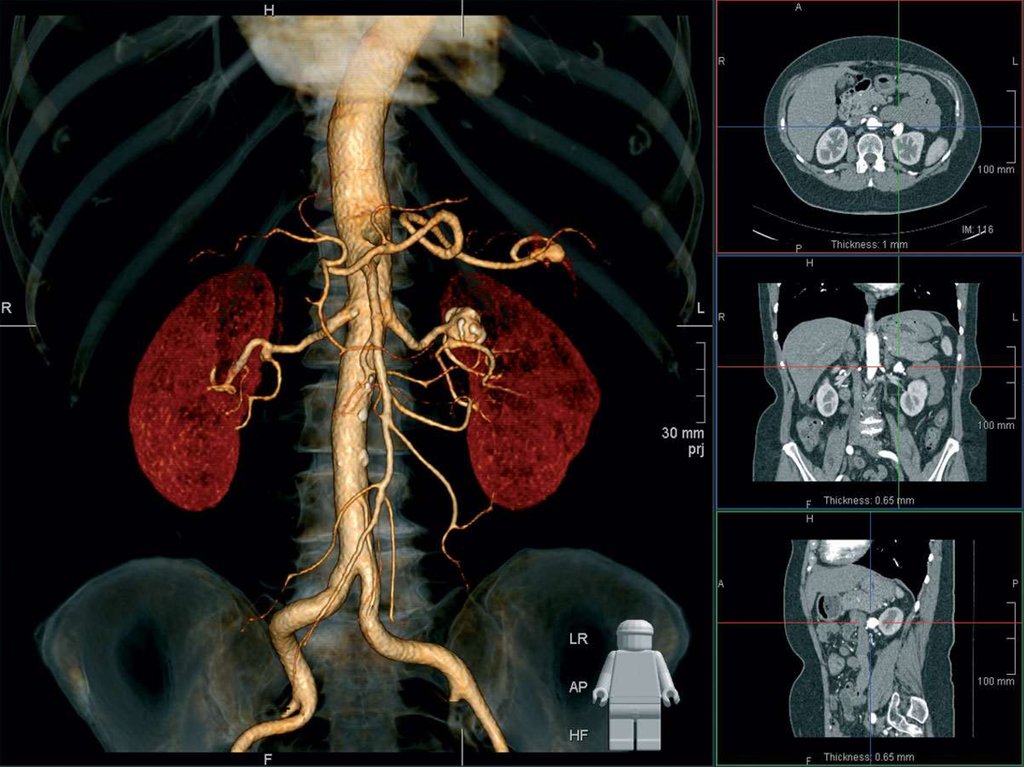

биопсия почек